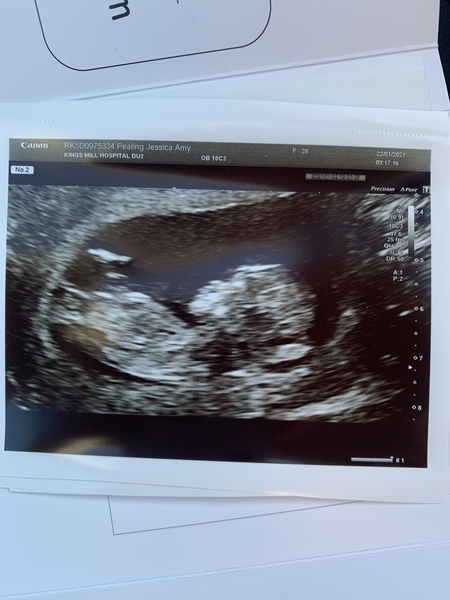

Jessicapebbles · 22/01/2021 11:42

Hi guys! I had my 12 week scan this morning and baby is doing very well. Had to eat some chocolate and wiggle lots to wake him/her up.

August 2021 - Scans and booking in!

Beautiful scan too @Jessicapebbles, congratulations 😊💝 xx

Ahh @Jessicapebbles such a lovely scan photo! You must be so pleased.

@Jessicapebbles gorgeous scan!!!!!! 🥰

@Jessicapebbles lovely pic from you too! (And a nice bonus that you got chocolate too!)

@biscuitcat @Thisisbananas3 @LBunz @Miniheart @PurplePansy05 Thank you ☺️ The chocolate was a bonus!